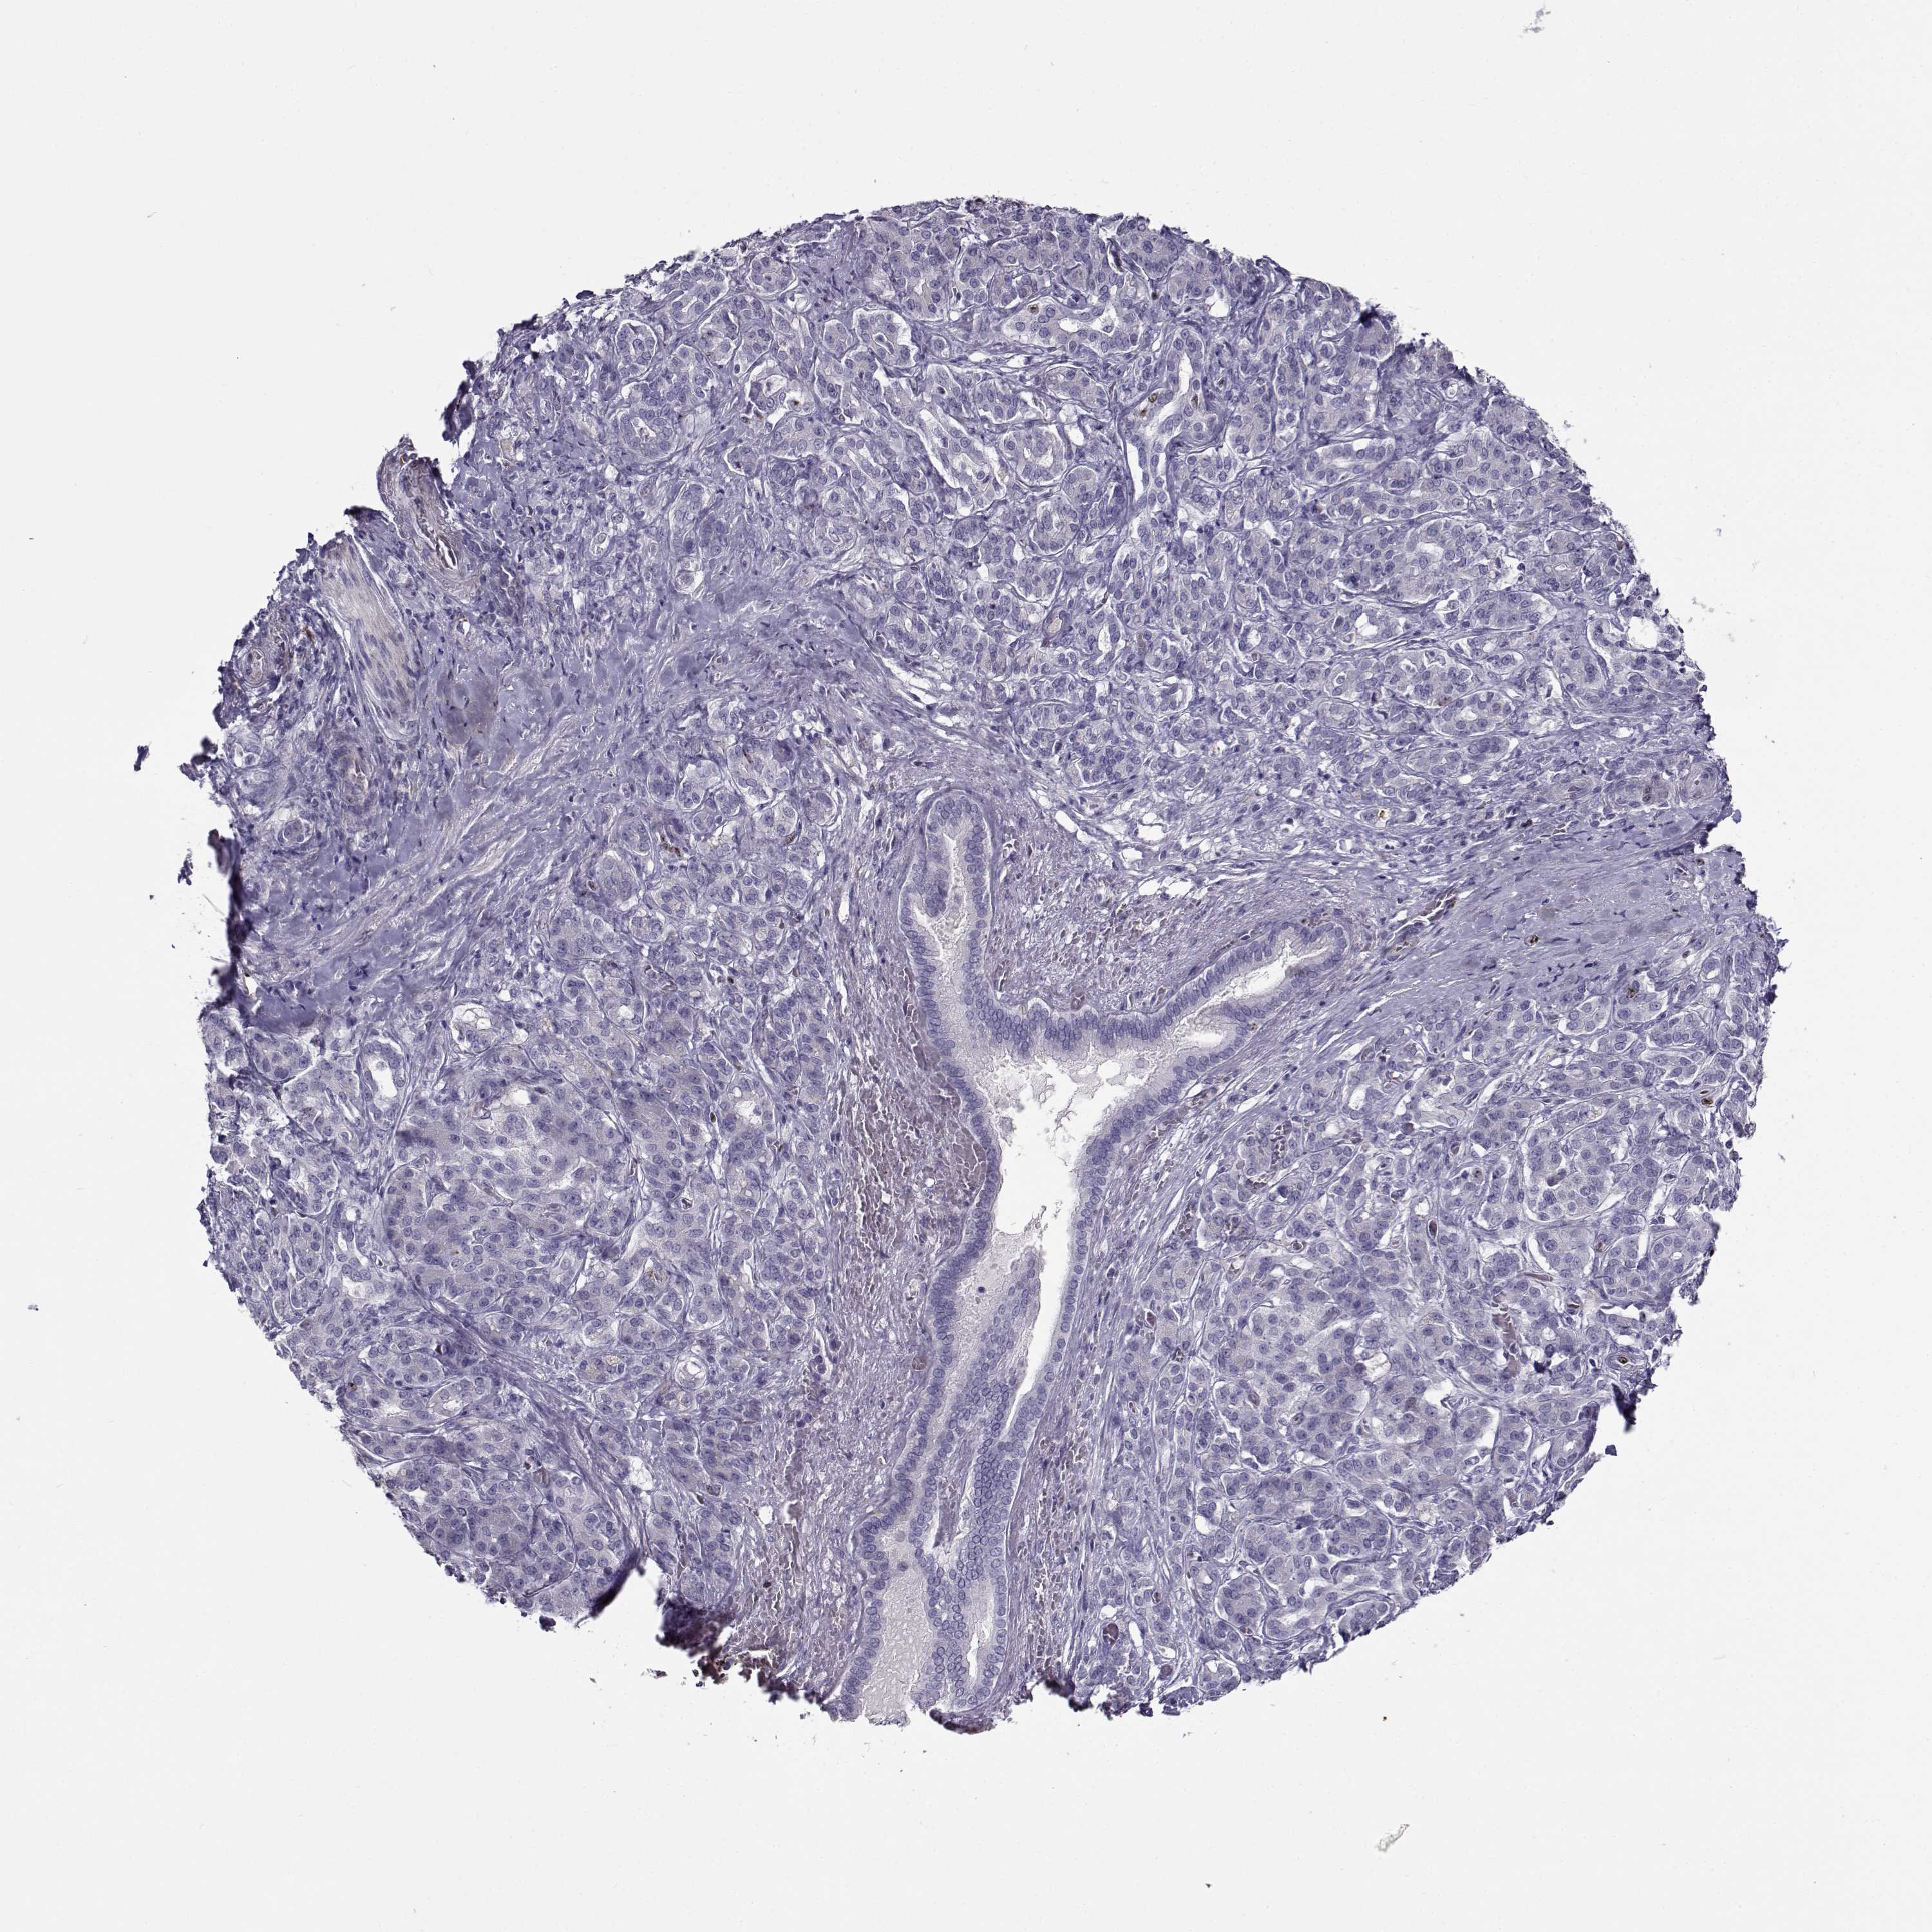

PANCREATIC CANCER - Protein expressioni

A mouse-over function shows sample information and annotation data. Click on an image to view it in a full screen mode. Samples can be filtered based on level of antibody staining by selecting one or several of the following categories: high, medium, low and not detected. The assay and annotation is described here.

Note that samples used for immunohistochemistry by the Human Protein Atlas do not correspond to samples in the TCGA dataset.

Antibody stainingi

Antibody staining in the annotated cell types in the current human tissue is reported as not detected, low, medium, or high, based on conventional immunohistochemistry profiling in selected tissues. This score is based on the combination of the staining intensity and fraction of stained cells.

Each image is clickable and will lead to virtual microscopy that enables deeper exploration of all samples and also displays staining intensity scores, fraction scores and subcellular localization as well as patient and tissue information for each sample.

Antibody HPA064874

Staining

High

Medium

Low

Not detected

Intensity

Strong

Moderate

Weak

Negative

Quantity

>75%

75%-25%

<25%

None

Location

Nuclear

Cytoplasmic/membranous

Cytoplasmic/membranous,nuclear

Adenocarcinoma, NOS